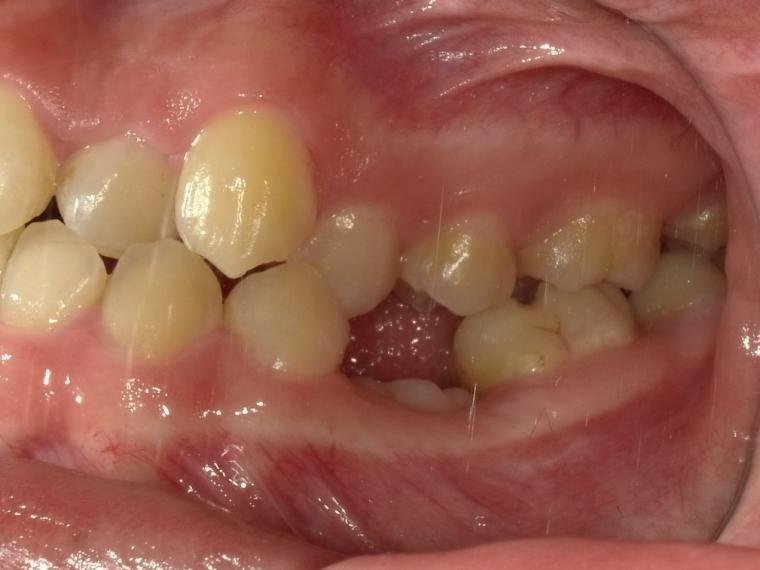

BEFORE

下顎第二小臼歯が先天性の欠損の患者さんです。

乳歯が生えていましたが、状態が悪くなり抜歯となりました。

他の歯の健康を考えマウスピース矯正で歯列を整えてからインプラントを1本埋込しました。